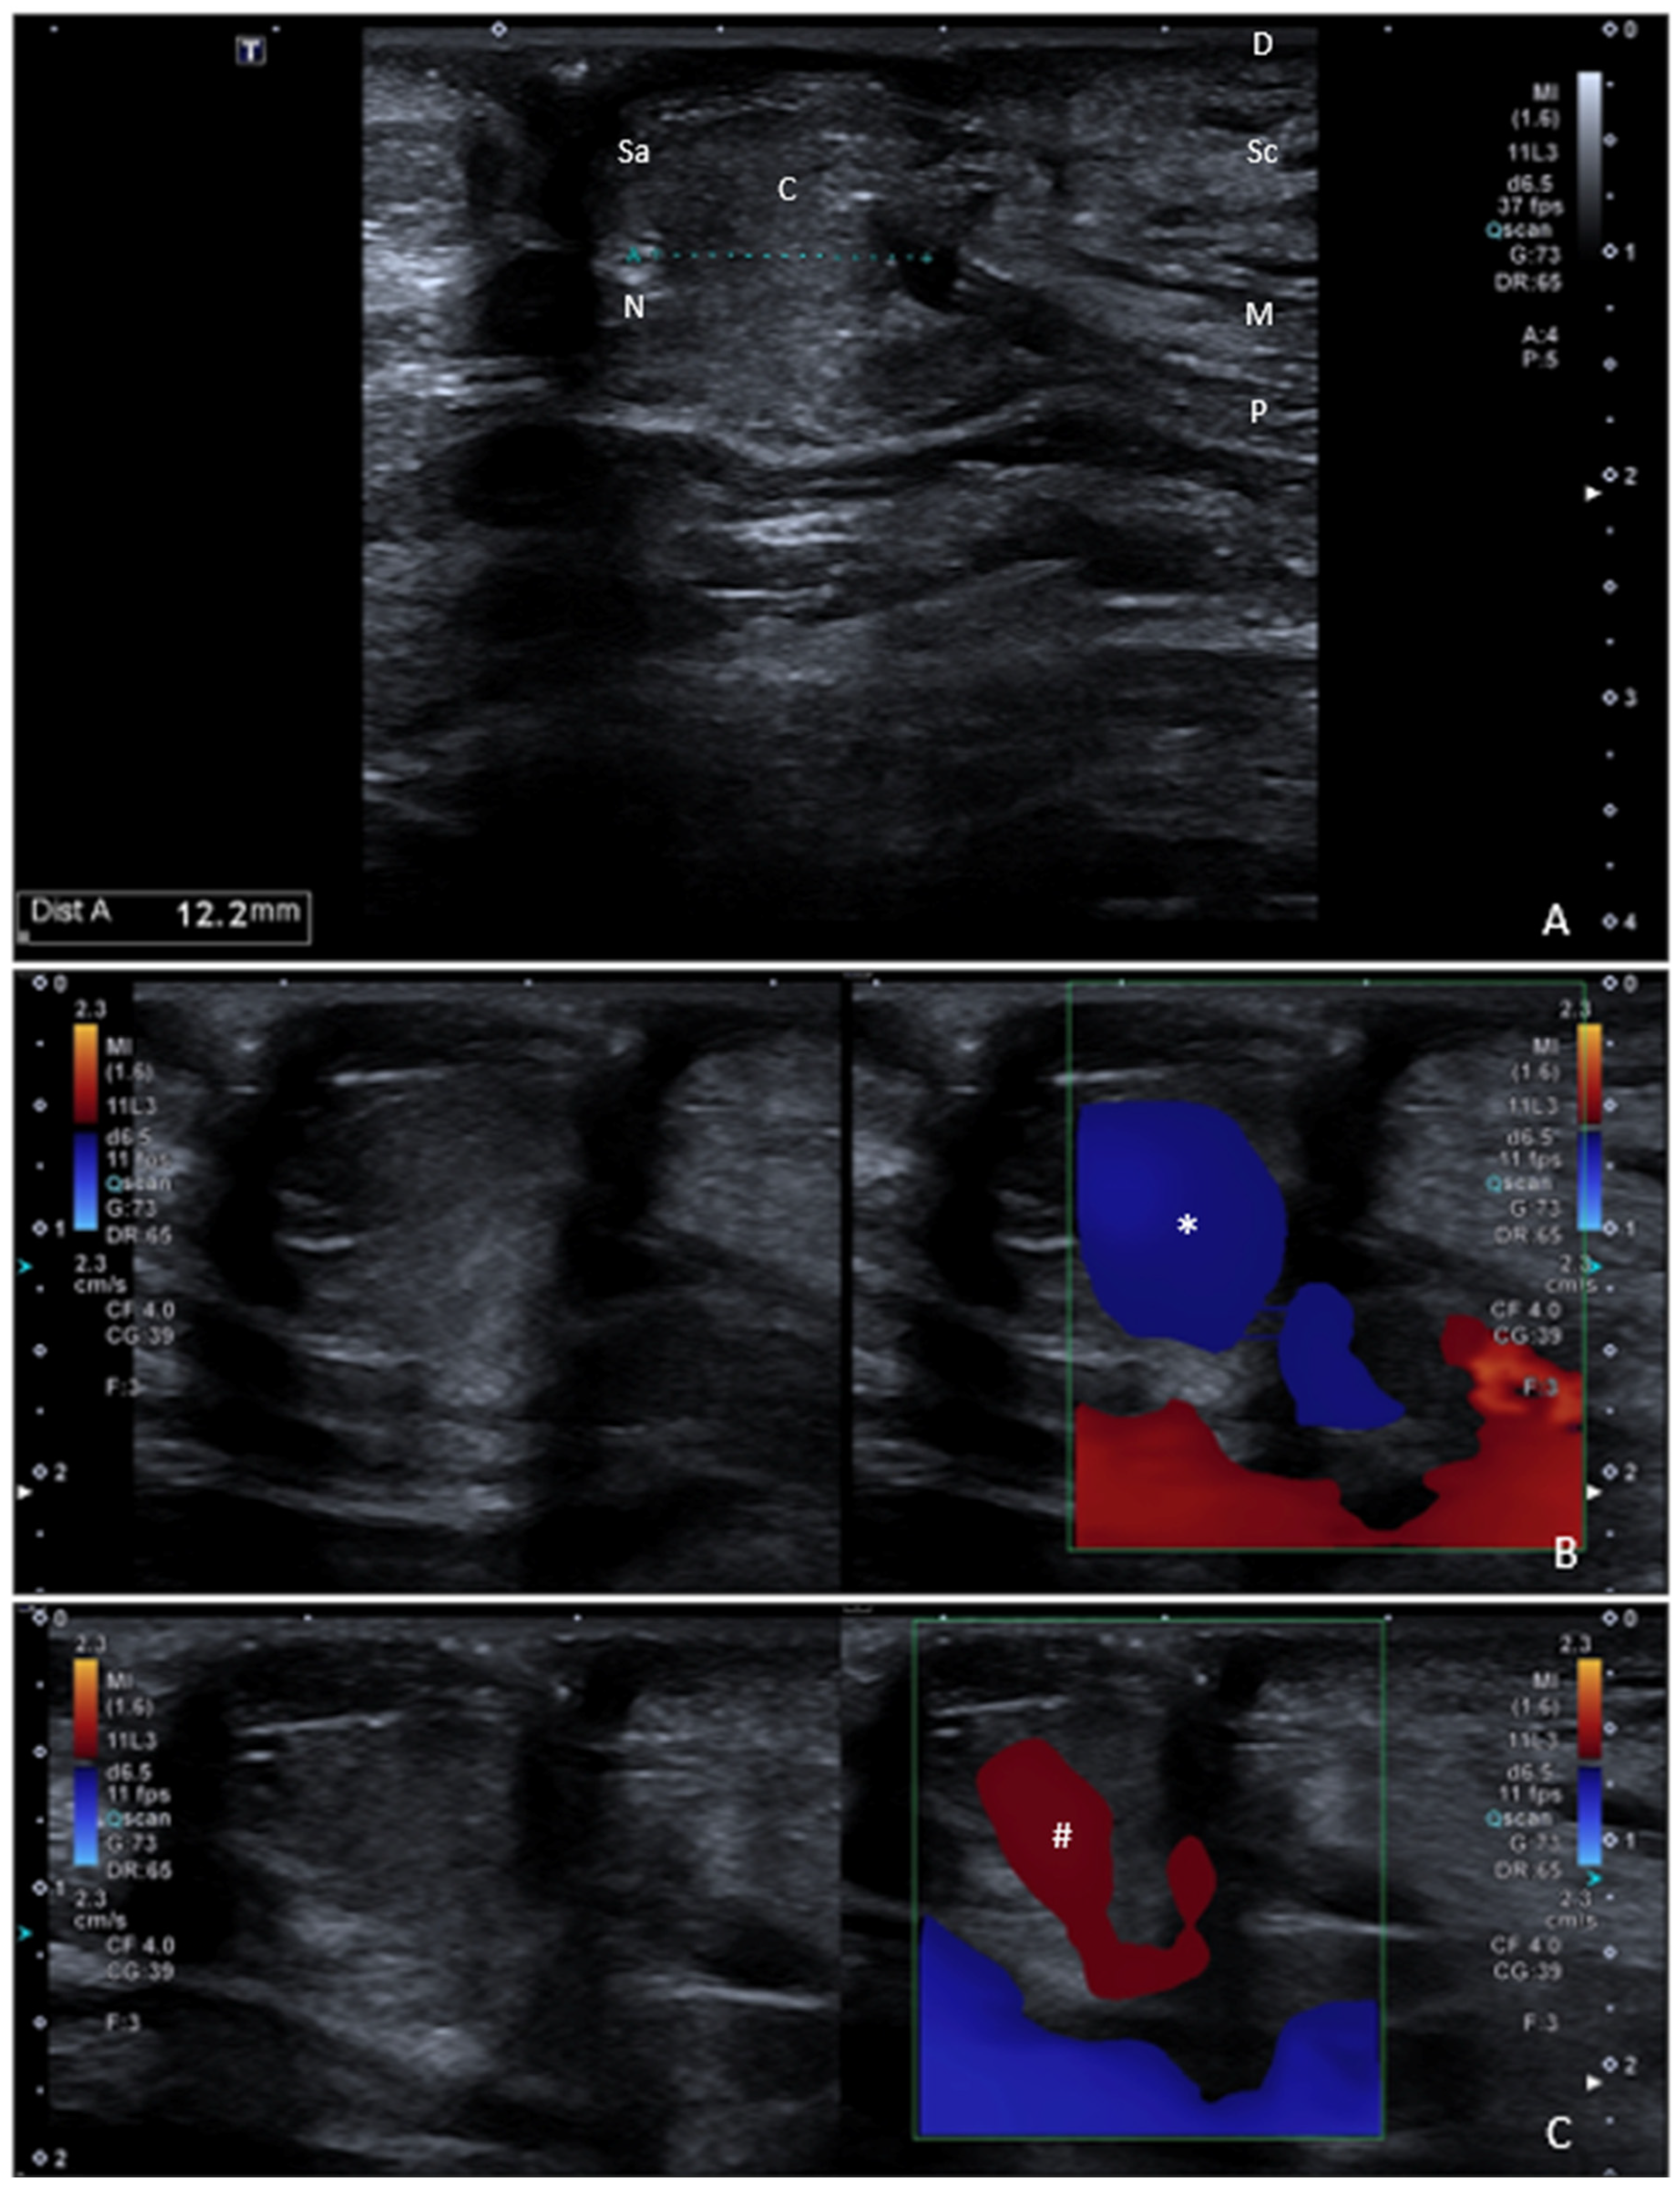

Umbilical Hernia Probe-Induced Cocco Sign: Color Doppler During Pressure and Release in Standing Position

- Cocco, G. Dynamic color Doppler assessment for the detection of small abdominal hernias: The “Cocco Sign”. J. Ultrasound. 2025. [Google Scholar] [CrossRef] [PubMed]